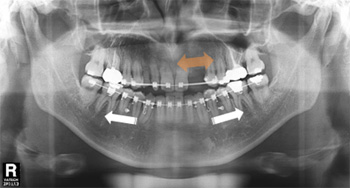

아랫니가 앞니보다 바깥쪽으로 위치한 증상을 바로잡고 빠진 윗니를 수복하기 위해 내원한 37세 남성입니다. 검사 결과 위쪽 영구치 3개 결손 된 상태였으며, 아래턱이 전방 위치된 주걱턱(골격성 3급 부정교합)으로 진단 하였으나 양악수술 없이 치료를 원하셔서 치아교정과 임플란트 치료를 병행하였습니다.

① 결손된 위 앞니, 송곳니 공간 재형성

② 교정용 미니스크류를 이용하여 아래 전체 치열 후방 이동

약 2년 간의 교정 치료 후 정상적인 앞니 배열과 임플란트 식립에 필요한 공간이 확보되어 보철 치료를 한 후 교정 장치를 제거하였습니다. 거꾸로 물려 정상적인 기능이 어려웠던 앞니의 심미적, 기능적 회복이 동시에 이루어졌습니다.